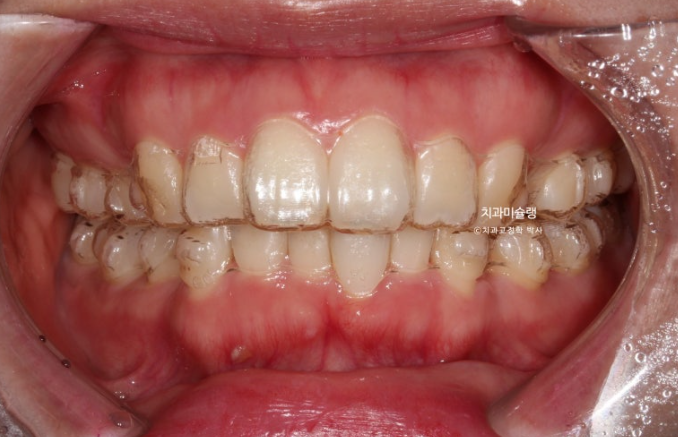

중심선은 잘 맞으며 과개교합을 개선하기 위한 교정용 나사를 심고 진행했습니다.

상악 발치공간이 양측으로 각각 1mm씩 남은 상태라서 재제작에 들어갔습니다.

발치공간이 소량 남은 것 이외에 치아 뿌리 평행도도 양호하고 어금니 쓰러짐도 없이 잘 진행된 편이라 이때까지만 해도 토탈 치료기간이 토탈 2년을 넘지 않을 것으로 예상했습니다.